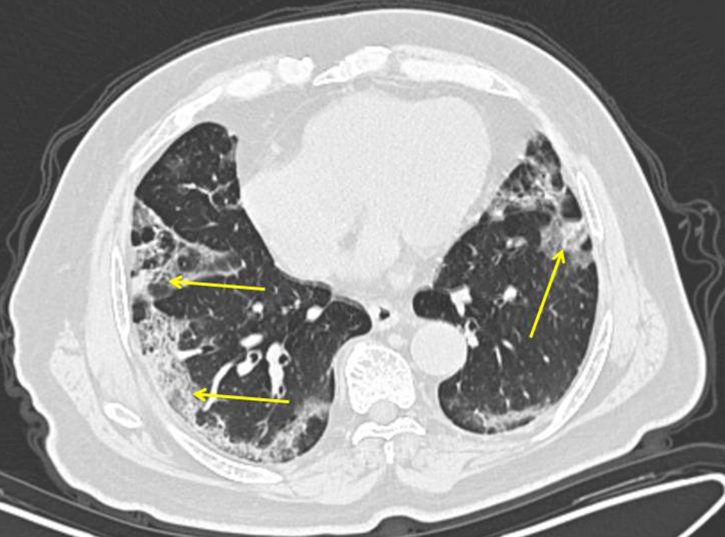

Naučni članak objavljen u Annals of Internal Medicine kaže da su snimci pluća asimptomatskih pacijenata pokazali određene abnormalnosti na plućima.

Tačnije, našli su ono što radiolozi nazivaju "mlečno staklo" koje se uglavnom javlja u donjem delu pluća, ali to ne mora uvek da bude slučaj. Ovaj naučni tekst tvrdi da se "mlečno staklo" javlja u 54 odsto asimptomatskih pacijenata.

- "Mlečna pluća" nisu neuobičajena i postoji nekoliko uzroka za njih. Međutim, mlečno staklo nastalo usled Kovida-19 je drugačije. Oblik je okrugao i raspoređeni su po krajevima pluća, što je neuobičajeno - kaže Adam Bernejm, radiolog iz Mount Sinai bolnice u Njujorku.